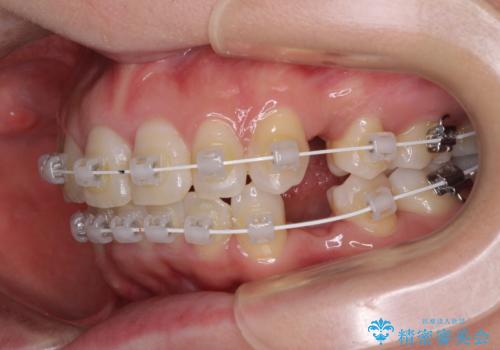

インビザラインが続けられない ワイヤー装置による抜歯矯正

- 矯正装置

- インビザライン・審美装置

2年ほどインビザラインを使用しましたが、どうしても歯の移動がマウスピースに追随せず、全顎ワイヤー矯正へ切り替えました。

ワイヤー装着後は2年弱で、しっかりと仕上げることができました。